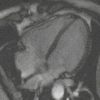

Cardiovascular

MR angiogram in congenital heart disease

Cardiac MRI is complementary to other imaging techniques, such as echocardiography, cardiac CT, and nuclear medicine. It can be used to assess the structure and the function of the heart.[40] Its applications include assessment of myocardial ischemia and viability, cardiomyopathies, myocarditis, iron overload, vascular diseases, and congenital heart disease.[41]